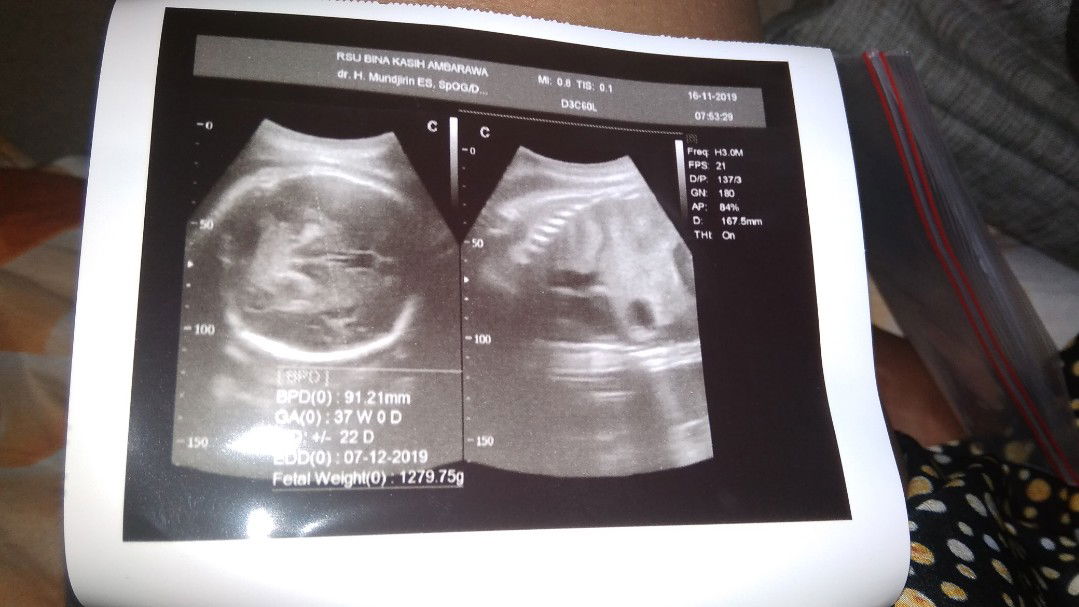

USG

Assalamualaikum bunda, disini ada yg bisa baca hasil USG ga, biar tau berat badan debay itu yg mana ya soalnya saya bingung dan ga ngerti juga yg mana.. usia kehamilan 37w 4d. Terimakasih